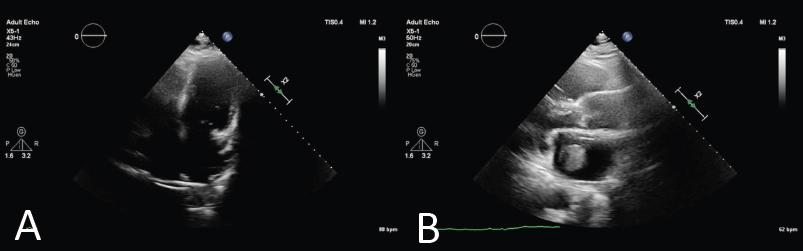

Figure 1